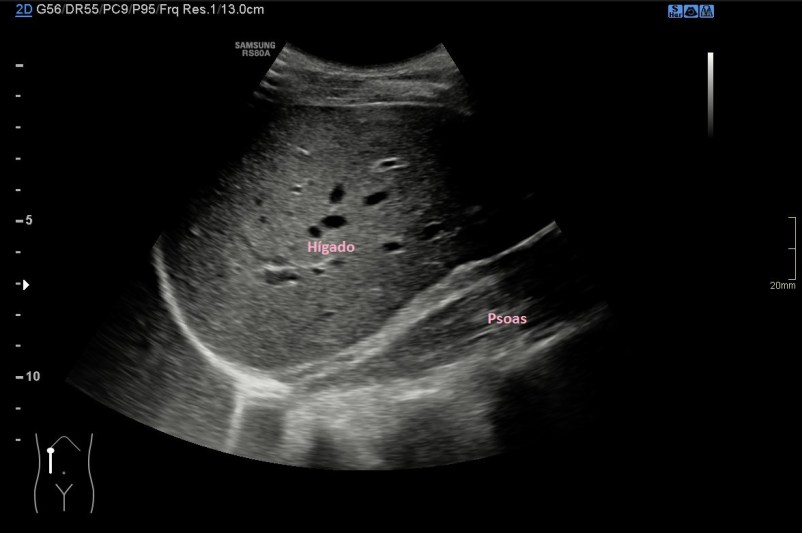

Bueno pues al explorar el lugar donde habitualmente encontramos en riñón derecho, encontré la imagen 2. Compara con la 2a. El paciente mostraba una fosa renal derecha vacía, donde el hígado y el psoas aparecían con semiología normal, pero donde clarísimamente faltaba el riñón. En estos casos hay que pensar en varias causas:

Resolvemos al final y sigo con la explicación haciéndonos a la idea de que era la primera exploración de este paciente…Es evidente que en la imagen 2 observamos que falta el riñón y me aseguré de que no se encontraba ectópico, simplemente, certifiqué su ausencia dentro de toda la cavidad abdominal.